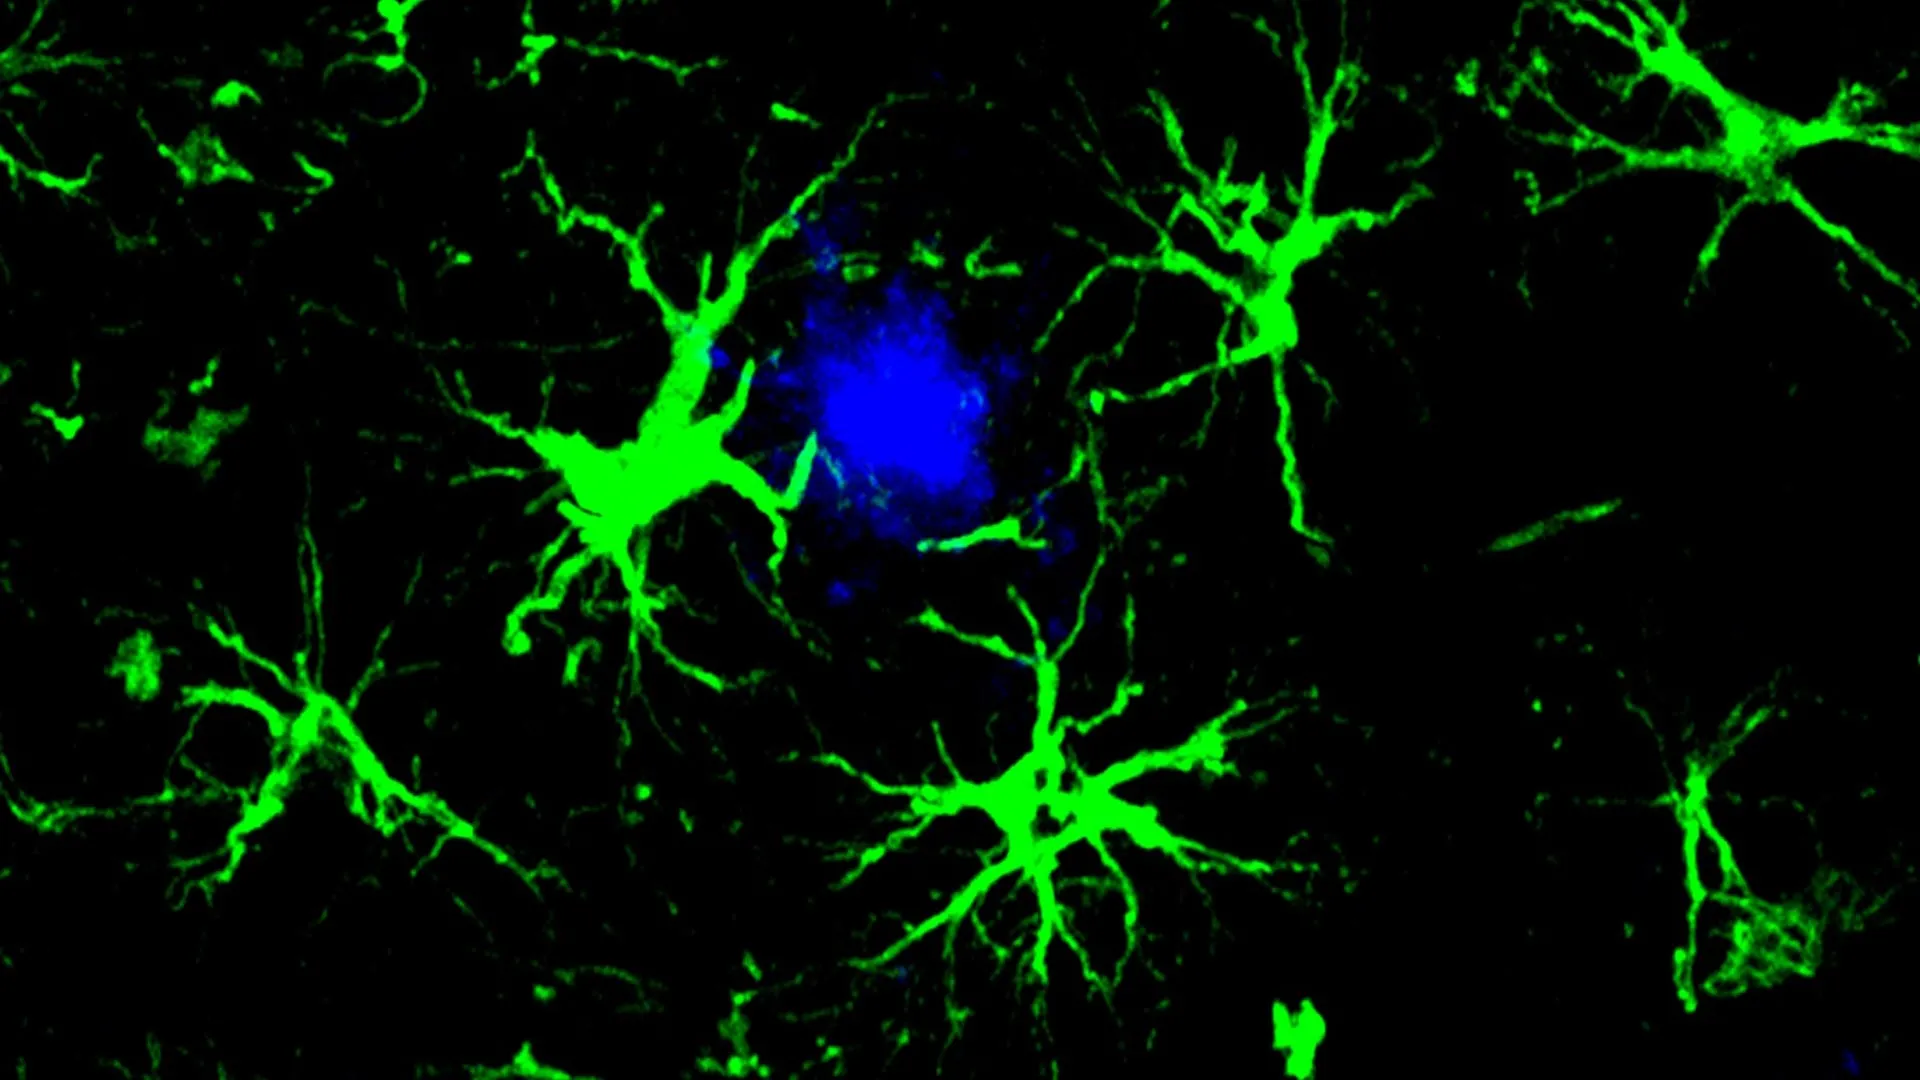

The cornerstone of this innovative strategy lies in the ingenious reprogramming of astrocytes, a fundamental type of glial cell abundant in the brain, transforming them into highly specialized amyloid-clearing agents. This concept draws inspiration from the highly successful chimeric antigen receptor (CAR) T-cell therapies that have transformed cancer treatment. In those therapies, a patient’s own immune T-cells are genetically modified to recognize and eliminate cancerous cells with remarkable precision. Applying this principle to Alzheimer’s, scientists have ingeniously equipped astrocytes with a CAR "homing device." This engineered component enables the astrocytes to specifically identify and bind to amyloid plaques, subsequently initiating their breakdown and removal. Essentially, these reprogrammed CAR-astrocytes function as microscopic cleaning crews within the brain, diligently seeking out and eradicating the harmful amyloid-beta proteins that contribute to cognitive decline.

The research team, led by first author Yun Chen, PhD, sought to alleviate the pressure on these overworked microglia by focusing on astrocytes. As the most prevalent cell type in the brain, astrocytes play a vital role in maintaining the intricate balance and supportive environment essential for neuronal function. Dr. Chen, then a graduate student working under the guidance of Drs. Colonna and David M. Holtzman, a leading Professor of Neurology at WashU Medicine, embarked on a mission to redesign astrocytes into potent amyloid-clearing agents. This was achieved by introducing a gene that encodes for a chimeric antigen receptor (CAR) into the astrocytes using a harmless viral vector delivered via injection to the mice. Once expressed on the astrocyte’s surface, the CAR acted as a highly specific anchor, allowing the engineered cells to latch onto and internalize amyloid-beta proteins. This newly acquired capability empowered the astrocytes to actively seek out and degrade amyloid-beta plaques in mice genetically predisposed to developing Alzheimer’s-like pathology.

The results in the younger mice were profoundly encouraging, demonstrating a complete cessation of plaque formation. By the six-month mark, a stage where untreated control mice exhibited brains heavily laden with amyloid plaques, the treated mice showed no detectable evidence of these detrimental deposits. In the older cohort of mice, those that started the study with pre-existing plaque burdens, the CAR-astrocyte therapy proved to be highly effective in reducing the existing amyloid load. The treated mice showed approximately a fifty percent reduction in amyloid plaque levels when compared to a control group that received a virus lacking the CAR gene, underscoring the specific therapeutic action of the engineered astrocytes.